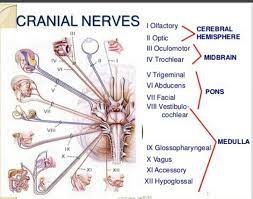

قیمت: 78٬000 تومان - دسته بندی فایل: پاورپوینتپاورپوینت معاینه ی اعصاب دوازده گانه مغزی(تشخیص عملی1)

فروش ویژه پاورپوینت حرفه ای معاینه ی اعصاب دوازده گانه مغزی با تخفیف استثنایی فقط 97 هزار تومان تعداد اسلاید : 42 اسلاید